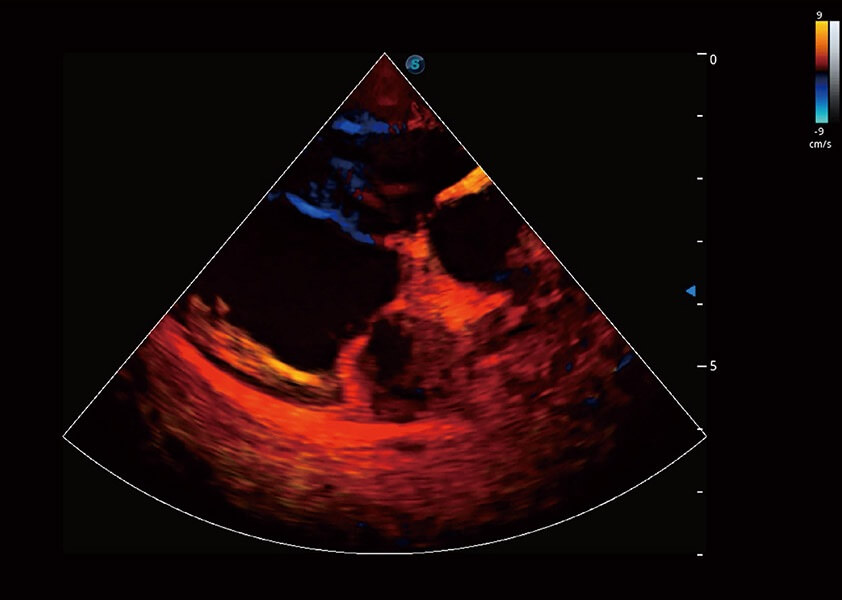

ProPet 60 作为一款高端台式动物超声设备,为动物医生的日常诊断提供了一系列贴合动物临床需求、解决临床实际问题的高级成像功能。凭借全系列高清探头,满足医生对腹部、心脏、生殖、浅表、肌骨等成像的所有需求,切实帮助您提升检查效率,提高诊断信心。

动物是人类最亲密的朋友和最值得信赖的伙伴。DB中国旗舰官方网站也一直致力于探索动物专用的超声影像解决方案。 全新推出的ProPet系列,是DB中国旗舰官方网站在动物超声影像智能化、专业化、精准化的一次跨越式革新。动物不能用言语来表述自己的不适,通过超声影像,ProPet系列搭建了动物医生与不同物种沟通的“桥梁”,为动物医生注入了“治愈之力”。